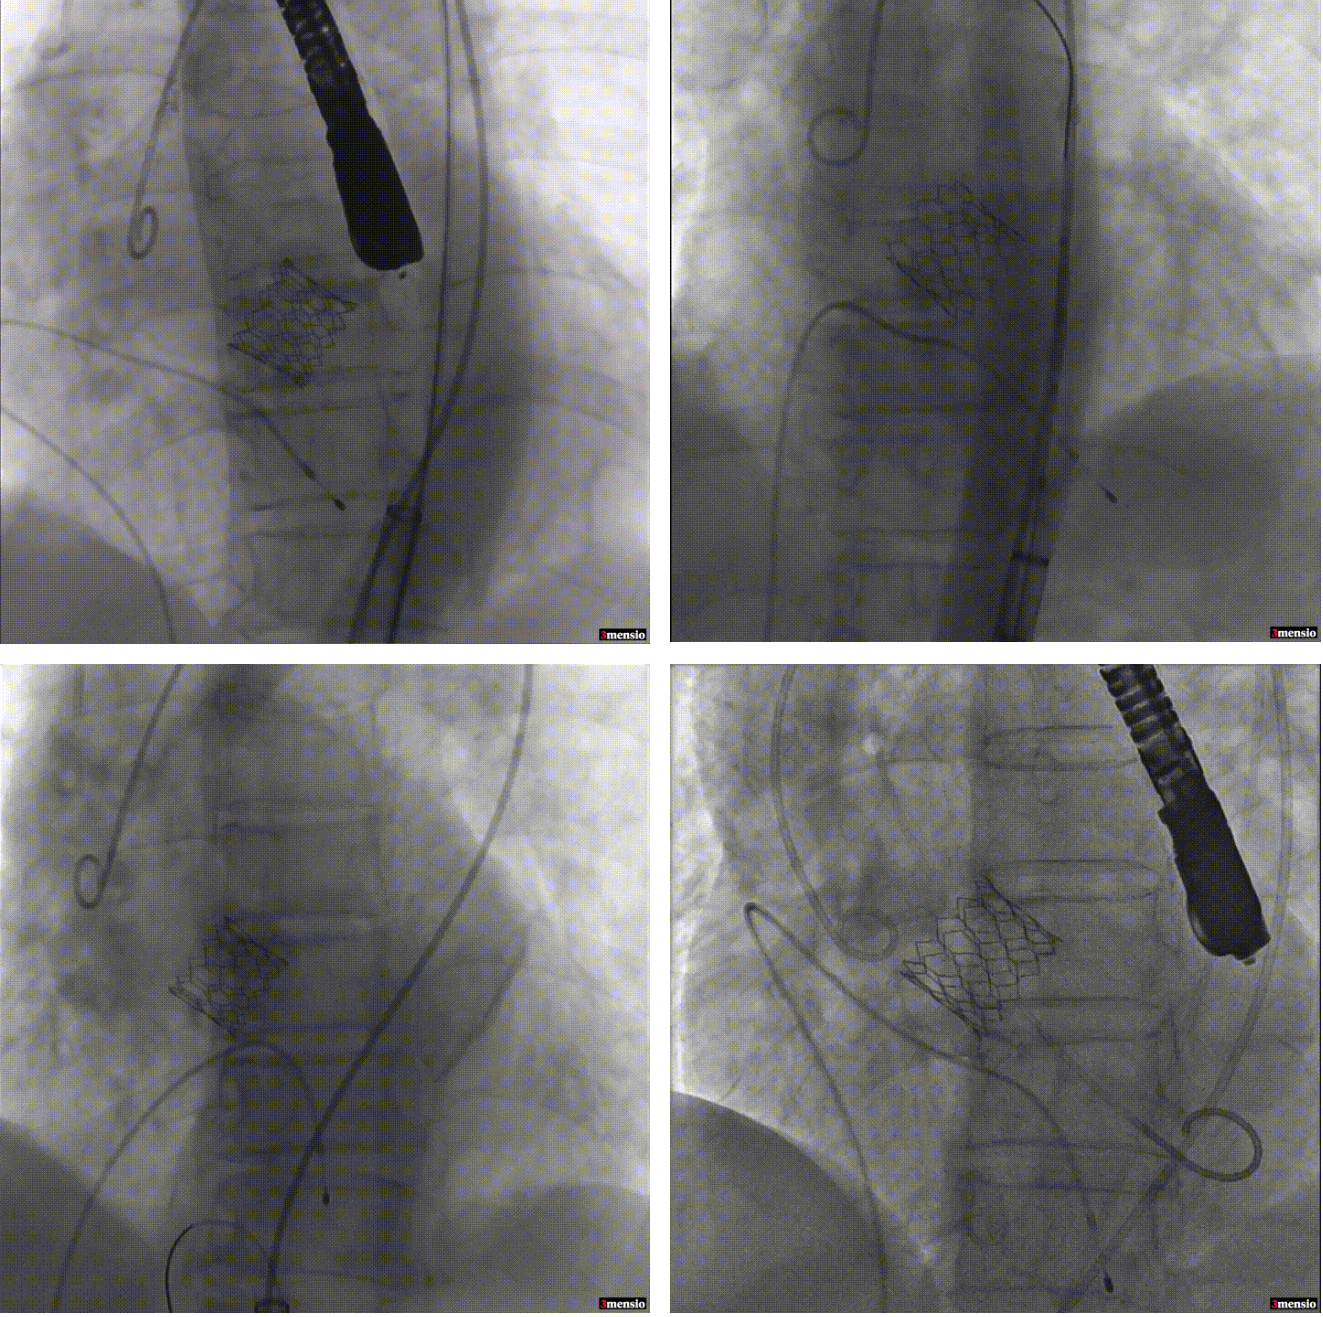

如下图所示,取得了极其满意的效果。

瓣膜释放 瓣膜释放后造影

现在最新型的球扩TAVI瓣膜在温州医科大学附属第一医院心脏外科成功顺利开展,取得满意的效果,拥有更好的手术效果及更低的风险,为主动脉瓣重度狭窄的患者带来福音。